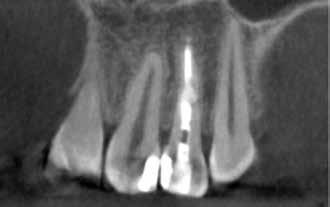

A kezelés befejezését követően 30 hónappal készített CBCT-felvételen a gyógyulás jelei észlelhetők.

MTA-val (Mineral Trioxide Aggregate; Harvard Dental) töltöttük fel. A léziótól koronális irányban elhelyezkedő gyökércsatorna-szakaszt meleg guttaperchával zártuk, majd az MTA-val kitöltött üregre egy kis darab kollagénszivacsot helyeztünk és a lebenyt varratok segítségével eredeti pozíciójában rögzítettük (12. a–b; 13. a–b. ábra). A fog koronai részét Gradia kompozit tömőanyaggal állítottuk helyre (GC; 14. a–b; 15. ábra). Kontrollvizsgálatra két (16. a–b ábra) és négy évvel (17. a–b ábra) később került sor. A kontrollfelvételeken a bukkális kortikális jelenléte volt észlelhető. A fog körüli parodoncium egészséges volt, valamint a páciens sem számolt be tünetekről.

16. a–b ábrák: A két évvel később készített kontroll CBCT-felvétel. – 17. a–b ábrák: A négy évvel később készített kontroll CBCT-felvétel.

Az IRR fennállásának gyanúja esetén mindenképp javasolt CBCT-felvétel készítése. A diagnosztizáláson kívül a kezelés pontos megtervezéséhez is rendkívül hasznosak a háromdimenziós felvételekből nyerhető adatok. Azt, hogy milyen stratégia mentén látjuk el a fogat, leginkább két fő tényező befolyásolja: A lézió alakja, és hogy van-e perforáció a gyökéren (1. táblázat). A fentiekben bemutatott esetek jól példázzák, hogy az egy ülésben végzett kombinált endodonciai és sebészi terápia alkalmas azon IRR-rel érintett fogak hosszú távú megtartására, ahol a gyökér már perforálódott és emellett a környező csontállomány is érintetté vált.